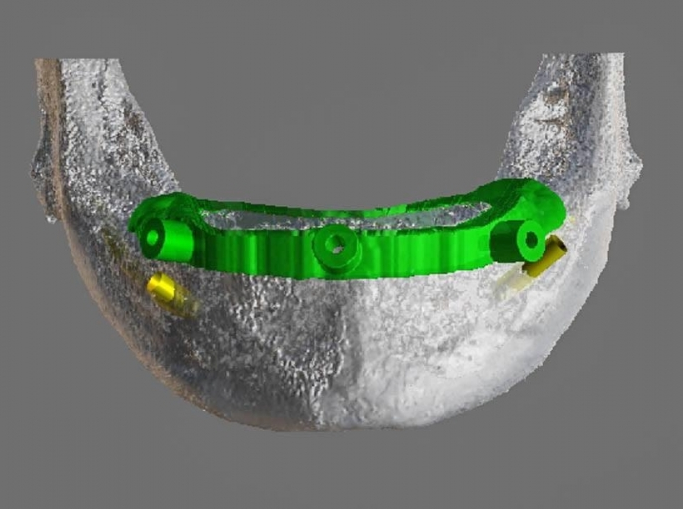

Vă prezentăm un caz All-on-4 finalizat cu succes cu ajutorul a 2 ghiduri chirurgicale realizate 100% cu ajutorul tehnologiei digitale.

Am folosit doua ghiduri: unul pentru osteoplastia crestei alveolare, iar cel de-al doilea pentru inserarea implanturilor.